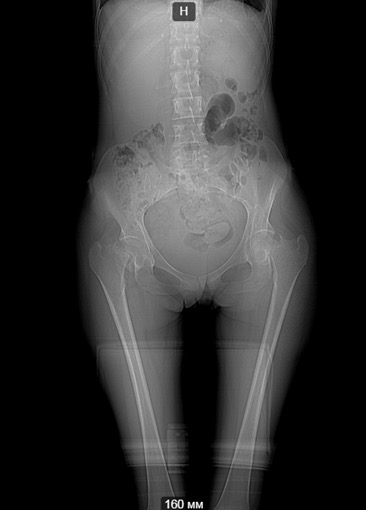

Клинический случай, больная Т. 30 лет, 40 кг, анамнез: Считает себя больной с начала декабря 2014 года, травмы отрицает, ни с чем не связывает. Со слов на фоне полного здоровья появились отеки всего тела, после чего боли в пояснице, правом к/с, затем т/б суставах. Обратилась за мед.помощью по месту жительства, анемия до 40 г/л. Произведена гемотрансфузия эр.взвесью, гемоглобин 100. При обследовании выявлена киста яичника, с подозрением на злокачественный процесс с mts в кости таза пациентка направлена на консультацию к онкологу. Злокачественный процесс исключен.

Направлена на консультацию к гематологу , выполнена стернальная пункция. Данных за миелому не получено. Больная в настоящее время проходит дообследование с перспективой для паллиативного (а может и нет?) протезирования т/б суставов. Из обследований: положительное RW, лечилась 10 лет назад. Гемоглобин 85, снижается, произведена гемотрансфузия до 100, формула б/о. Билирубин общ 47, прямой 9, по УЗИ, ФГС б/о. Т-лимфоциты 60,Т - хелперы - 20. Остальное в пределах нормы, легкие чистые. По МСКТ - дефект правой подвздошной. Как еще обследовать больную? на что похоже? Спасибо заранее за ответы

Не очень понятно насчет патологического характера перелома шеек бедра: на КТ есть локальное разрушение кости?

Кроме очага в подвздошной кости: есть ли другие? В этом может помочь сцинтиография с технецием.

Есть ли у нее история переломов в прошлом? Согласен с коллегами: возможна спортивная триада (анорексия, аменорея, остеопороз). Либо несовершенный остеогенез.